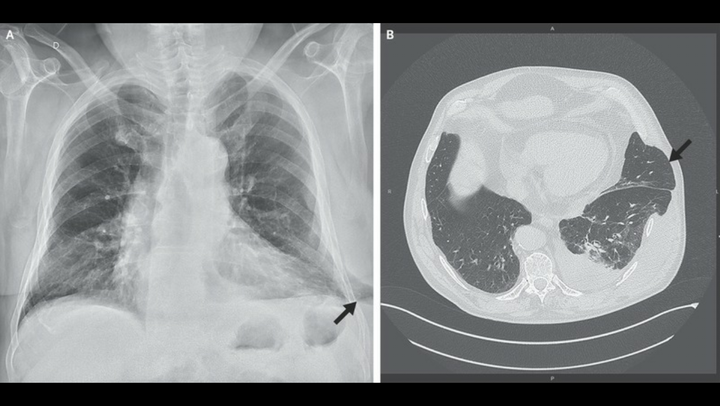

A 67-year-old man was admitted to the emergency department with a 10-day history of pain in the left side of the chest that had begun after an episode of severe coughing. He described persistent pain, without dyspnea, that was unrelieved by analgesic agents. He also noted swelling on the lower left side of the chest. The patient had a history of smoking, hypertension, and chronic obstructive pulmonary disease that required treatment with continuous positive airway pressure. There was no history of chest trauma or surgery involving the chest. Physical examination revealed thoracic asymmetry, with a soft, reducible mass corresponding to the region of swelling that was painful on palpation. The mass increased in size with inspiration and decreased in size with expiration. A radiograph of the chest showed extension of lung parenchyma beyond the rib cage laterally at the base of the left lung (Panel A, arrow). Computed tomography of the chest revealed lung herniation through a left lower intercostal space laterally, as well as a moderate pleural effusion on the left side (Panel B, arrow). The patient underwent successful surgical repair of the hernia.